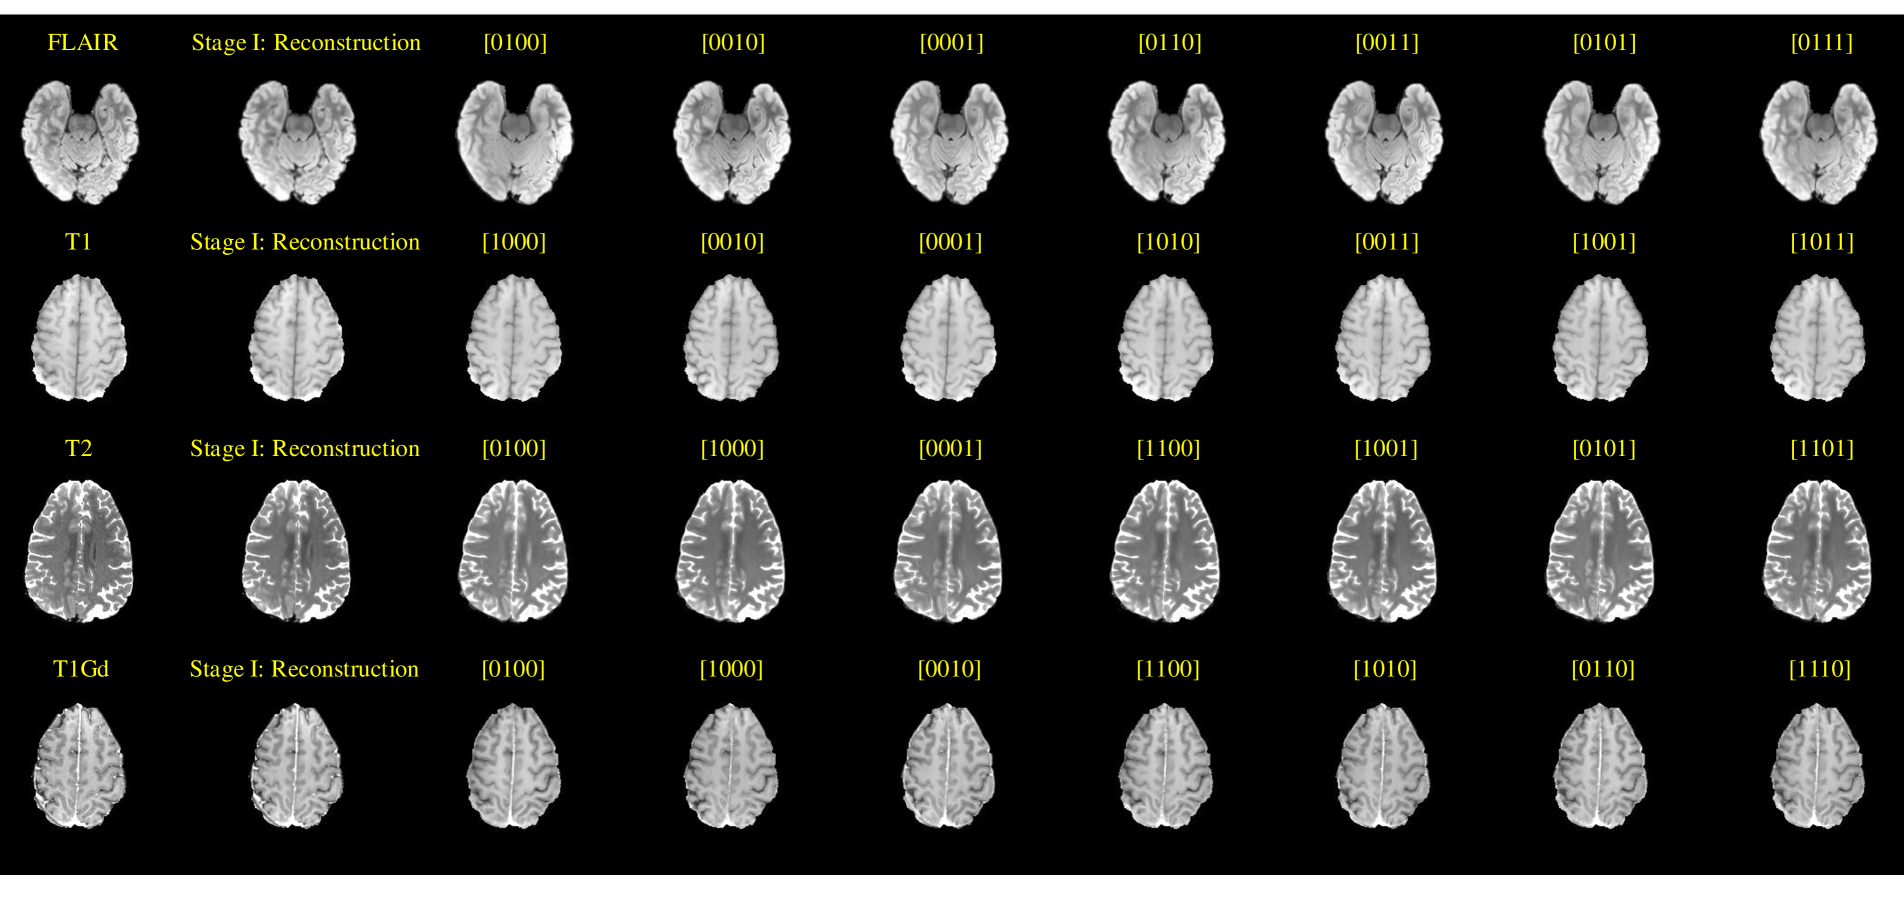

D Visual Results on BraTS 2023

Fig. B shows the reconstruction results (i.e., 2nd column) and imputation outcomes under various scenarios (i.e., 3rd to 9th columns) produced by our proposed CodeBrain model on the BraTS 2023 dataset. The results demonstrate that our model achieves unified brain MRI imputation while maintaining stability across different scenarios and modalities. However, despite its superior performance, the CodeBrain model struggles to capture the fine textures of the original modalities fully [20, 44]. Future work will focus on addressing this limitation to achieve high-fidelity brain MRI synthesis.

Refer to caption

Figure B: Reconstruction (i.e., 2nd Column) and imputation results in different scenarios (i.e., 3-9 Columns) of our proposed CodeBrain model for unified brain MRI imputation on the BraTS 2023 dataset. Here, the model captures most of brain structures and the imputed results in different scenarios remain stable.